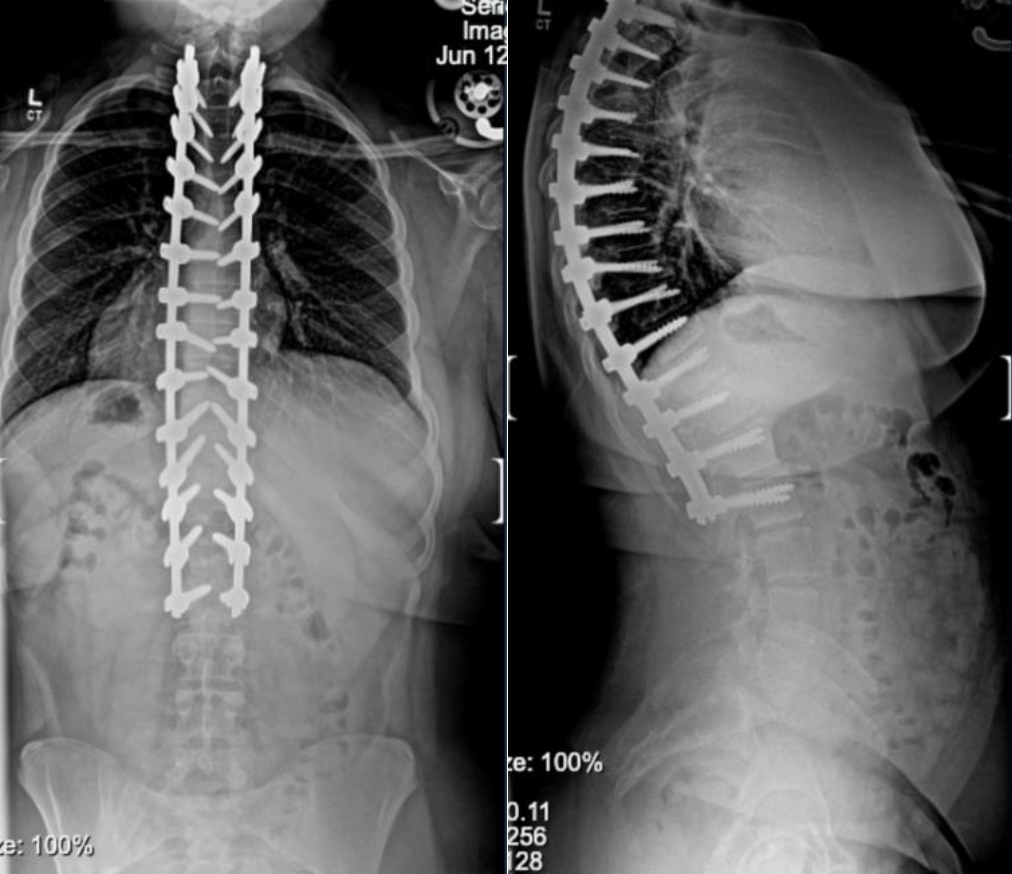

Below are before and after photos of two of our patients who underwent a posterior spinal fusion, one for scoliosis and one for kyphosis.

Kyphosis